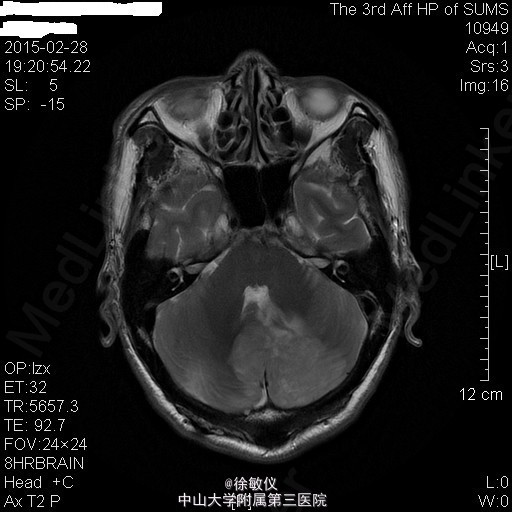

老年男性,主诉:咳嗽、咳痰2月余,头痛、纳差伴四肢乏力5天。 现病史患者2月余前无明显诱因出现咳嗽、咳痰,呈连声咳,咳白色稀薄痰,未予特殊治疗。5天前无明显诱因出现头痛,为右侧颞部持续性隐痛,尚可入睡,伴有纳差,四肢乏力。遂来我院门诊,查胸部CT示:1、左肺上叶尖后段空洞性病变;纵隔多发肿大淋巴结;中~大量心包积液。2、右肺中叶及双肺下叶少许慢性炎症。遂收入院。 查体:生命体征平稳,查体无特殊。 入院后予行心包穿刺抽液,心包积液检查:浆膜腔液总蛋白47.7g/L,乳酸脱氢酶306U/L,浆膜腔积液葡萄糖5.76mmol/L,白细胞计数2150X10E6,颜色黄色,粘蛋白定性试验+/-,红细胞计数1570X10E6,透明度微混,凝固物有凝块,淋巴细胞0.88,中性粒细胞0.12。血清 癌胚抗原>100ug/L。 血清乳酸脱氢酶:358U/L。 暂予头孢美唑钠(悉畅)注射剂2g Q12h,左氧氟沙星氯化钠(可乐必妥)注射液0.6g Qd抗感染治疗。 因患者诉头痛明显,行头颅MR提示:1右侧蝶骨嵴肿物,考虑脑膜瘤;双侧小脑半球及小脑蚓部肿物并双侧小脑半球脑沟脑回样强化,考虑转移瘤并脑膜转移,梗阻性脑积水。 诊断:1、心包积液 恶性肿瘤转移 2、高血压病 2级 高危 3、头部恶性肿瘤 颅内转移 4、脑膜瘤 5、肺部感染 患者肿瘤情况不明,出院后第二天因脑疝死亡。